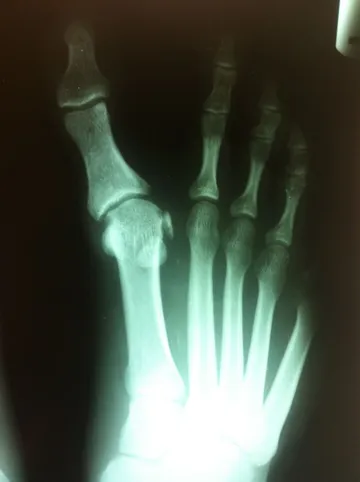

Hallux Varus Pre and Postop with 1st MPJ Fusion Below

Hallux Varus Postop and Preop with 1st MPJ Fusion Below

Deviation of the great toe off of the 1st metatarsal in long standing deformity with history of previous surgery as proof by the surgical screw at the base of the 1st metatarsal. The great toe joint (1st MPJ) is severly degenerated from arthritis (left). Surgical correction of this condition involves fusion of the joint with a cross screw technique (right) which will eliminate pain and difficult with walking and other activities.